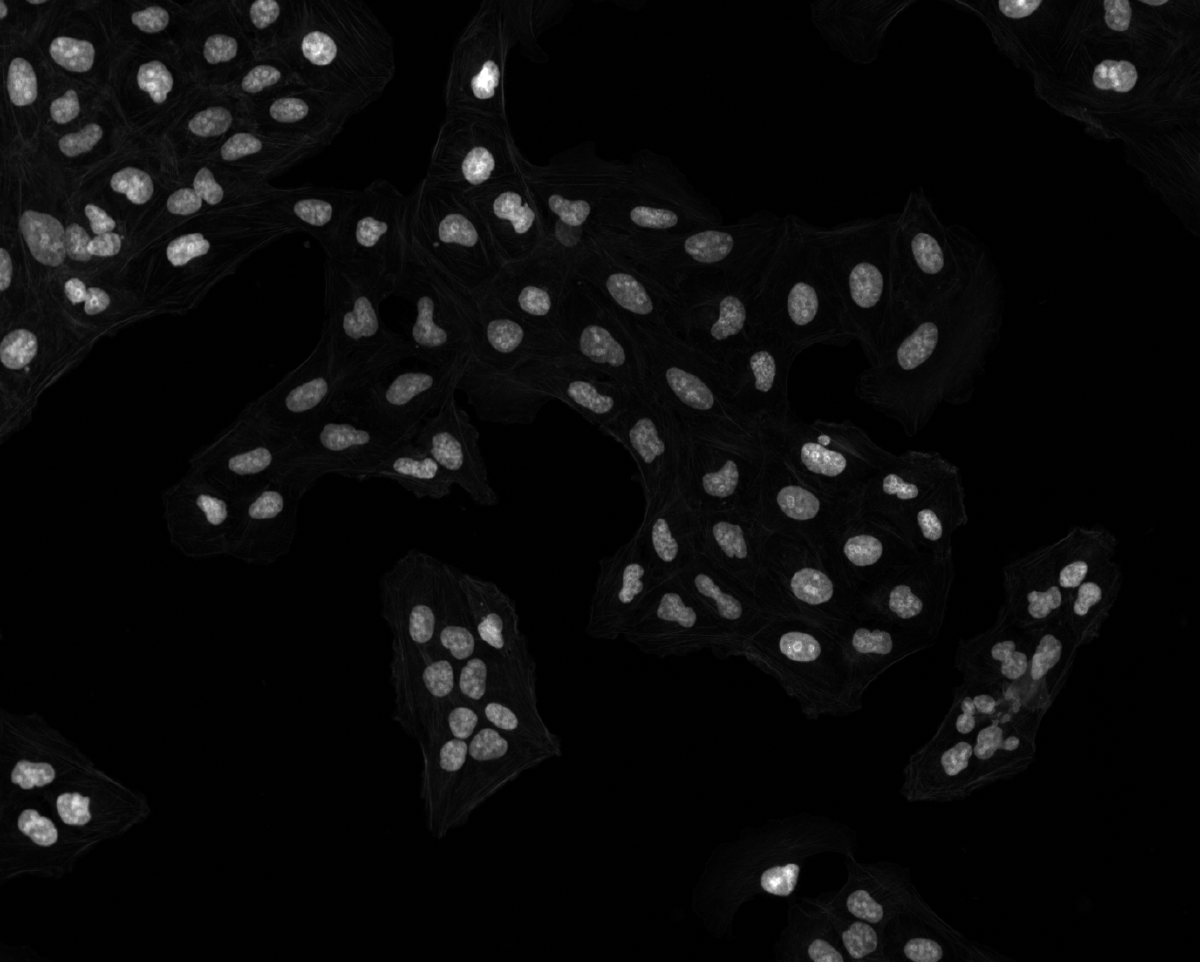

Open @tests/examples/Osteosarcoma_01.tif with Fiji

Fj Osteosarcoma_01.tif 1376×1104 · RGB · fluorescence

1376×1104 pixels; RGB